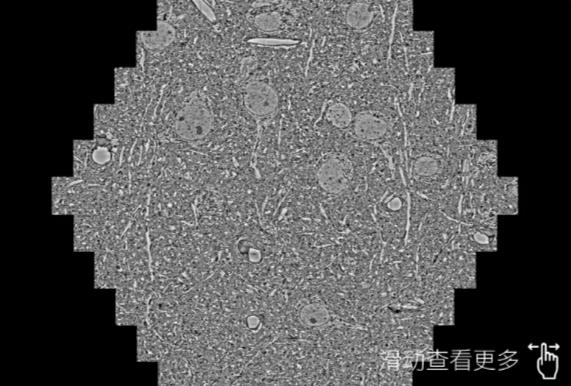

鼠脑切片。左图使用宁河蔡司宁河扫描电镜MultiSEM706对165μmx143pm面积区域成像,耗时仅需1.5秒。右图为鼠脑切片中30μm区域放大效果。样品由芝加哥大学B.Kasthuri提供。